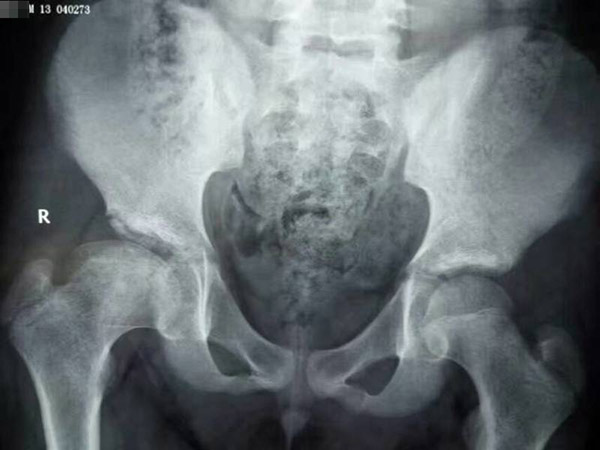

治疗后

在朋友的介绍下,亮亮的父母来到郑州中医骨伤病医院,经过不到两年的治疗,今年14岁的亮亮完已经全康复了。医生告诉他的父母,不用担心什么后遗症,现在亮亮好了完全是因为你们家长的这份心,如果不是当初的坚持,也不会有今天的结果。

门诊主任龚晓霞指出:儿童股骨头坏死,又称股骨头骨骺软骨炎或扁平髋。这个疾病是不能消极等待股骨头自愈,需要积极主动采取治疗的。儿童在发育期,儿童骨骼变化最快,如果不积极治疗失去最佳治疗时机,儿童就会留下终身跛行症状了。为了避免造成遗憾,我们需要最及时采取治疗,因为儿童股骨头坏死后骨骺生长软骨并没有完全被破坏掉,而骨骺是负责骨骼生长的,所以及时给儿童股骨头坏死患者治疗,可以及时修复坏死股骨头,并且其余剩下的骨骺还能生长,使股骨头逐渐长大恢复原状。儿童股骨头不像成人坏死股骨头不能长大,而是能够长大恢复成正常的股骨头,走路不瘸,髋关节功能正常。